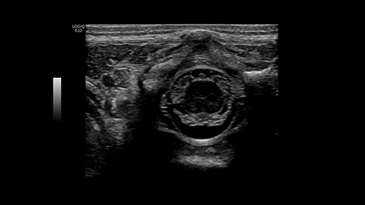

Образование яичника с 3D визуализацией методом HDlive, RIC5-9-D